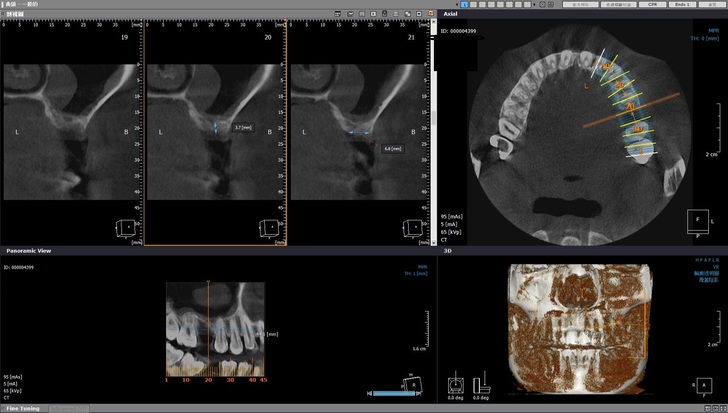

醫師會先在首次看診先拍攝X光片及斷層掃描

X光片是2D顯影

斷層掃描是3D顯影可以看到皮膚下骨頭層次

先用2D確認牙齒骨頭缺損情況及周圍鄰牙健康問題

再看3D來評估缺損牙齒位置需要補上多少人工骨粉才能使植牙穩固